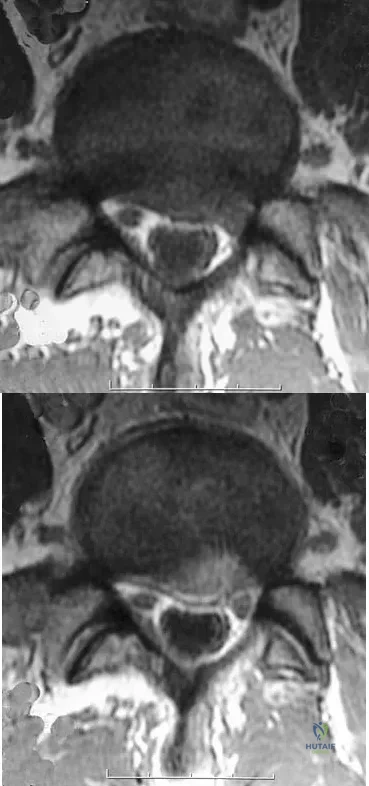

A 33-year-old woman sustains a C6 burst fracture diving into a swimming pool, resulting in a complete spinal cord injury. The canal compromise is shown in Figures 8a and 8b. Functional recovery would be maximized with